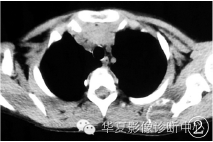

CT片:左侧肩胛骨局部见椭圆形膨胀性骨质破坏缺损,最大截面约4 cm×3 cm,其内填充略低密度灶(图2),边缘见骨壳包裹,边界清楚;

图2 肩部CT平扫示:左肩胛骨囊样膨胀性骨破坏区,骨壳薄,其内密度略低,似见分层